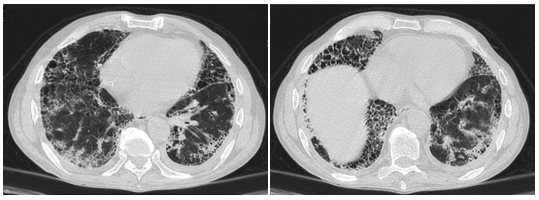

Sebastián Lamot: En la TC de tórax actual,

comparada con la anterior, se observó marcada

progresión. Se evidenció engrosamiento reticular

subpleural, panalización, bronquiectasias y bronquiolectasias por tracción de predominio en lóbulos

inferiores y la língula, consistente con patrón de

UIP definitiva1-3.